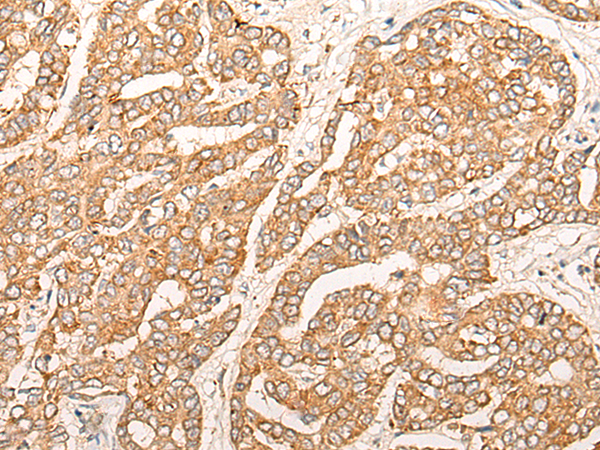

The image is immunohistochemistry of paraffin-embedded Human liver cancer tissue using (CPNE7 Antibody) at dilution 1/20. (Original magnification: ×200)

The image is immunohistochemistry of paraffin-embedded Human ovarian cancer tissue using (CPNE7 Antibody) at dilution 1/20. (Original magnification: ×200)